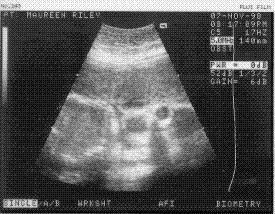

(above is an image of Baby "A" taken today,

lying sideways,head on the right and body on the left,

with its mouth wide open, and its right eye visible)